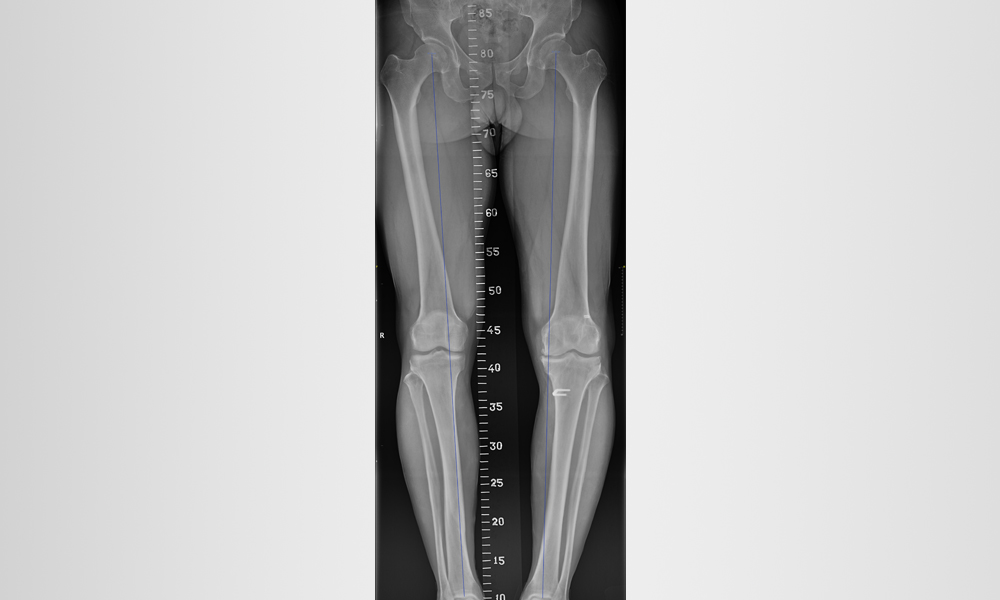

Diz ve bacağınızın kemikleri düzgün hizalanmadığında osteoartrit gelişebilir. Bu, dizinizin iç (medial) veya dış (lateral) tarafına fazladan baskı uygulayabilir. Zamanla bu ekstra basınç, kemikleri koruyan pürüzsüz eklem kıkırdağını aşındırarak dizinizde ağrı ve sertliğe neden olabilir.

X ışınları dizde normal eklem boşluğunu ve dizin bir tarafında osteoartriti gösterir. (Sol) Sağlıklı bir dizin bu röntgeni tibia ve femur arasındaki normal eklem boşluğunu gösteriyor. (Sağ) Bu röntgende, osteoartrit dizin iç kısmına zarar vermiş. Tibia ve femur birbirine sürtünerek ağrıya neden olur.

- Eğri bacak dizilimini düzeltmek için